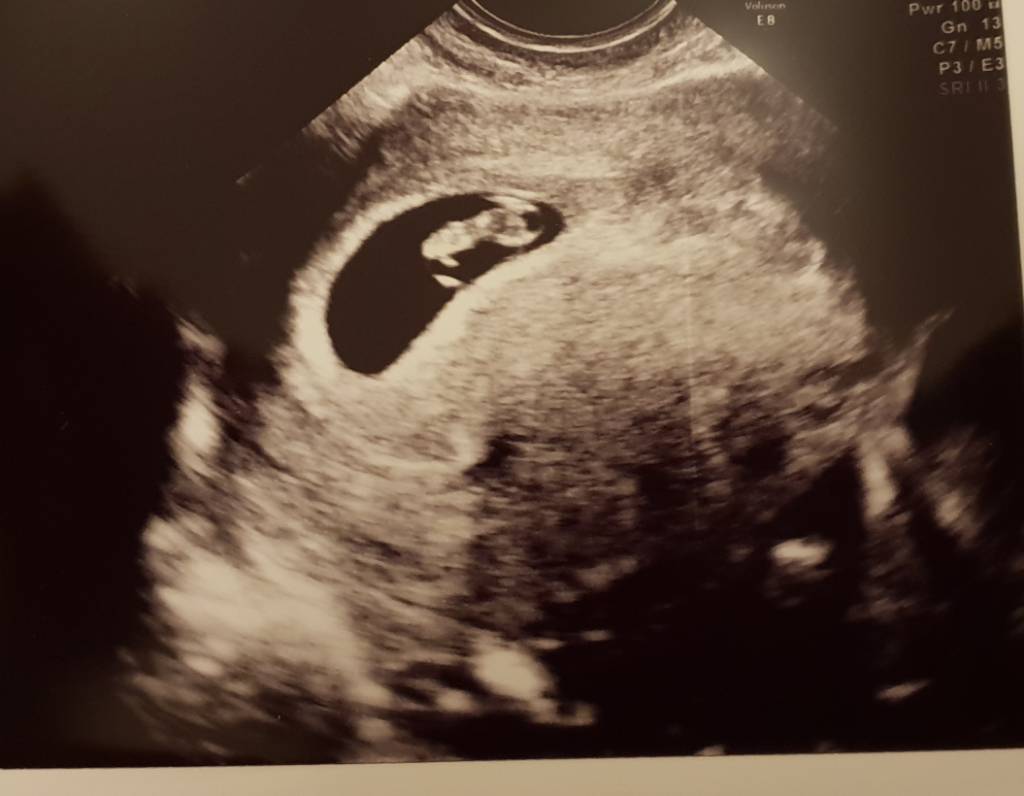

Kochane jestem po!!

Serduszko bije jak dzwon! Dzidzia ma 1.2 cm. Termin zostaje na 30 września.

Jestem taka szczęśliwa!!!

20190207_192140.jpeg